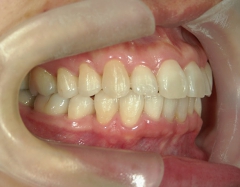

矯正歯科 治療後矯正歯科 プチワイヤー矯正 治療後矯正歯科(プチワイヤー矯正)治療後

矯正歯科 治療後 ミニインプラントを2本埋入し、下顎前歯を圧下